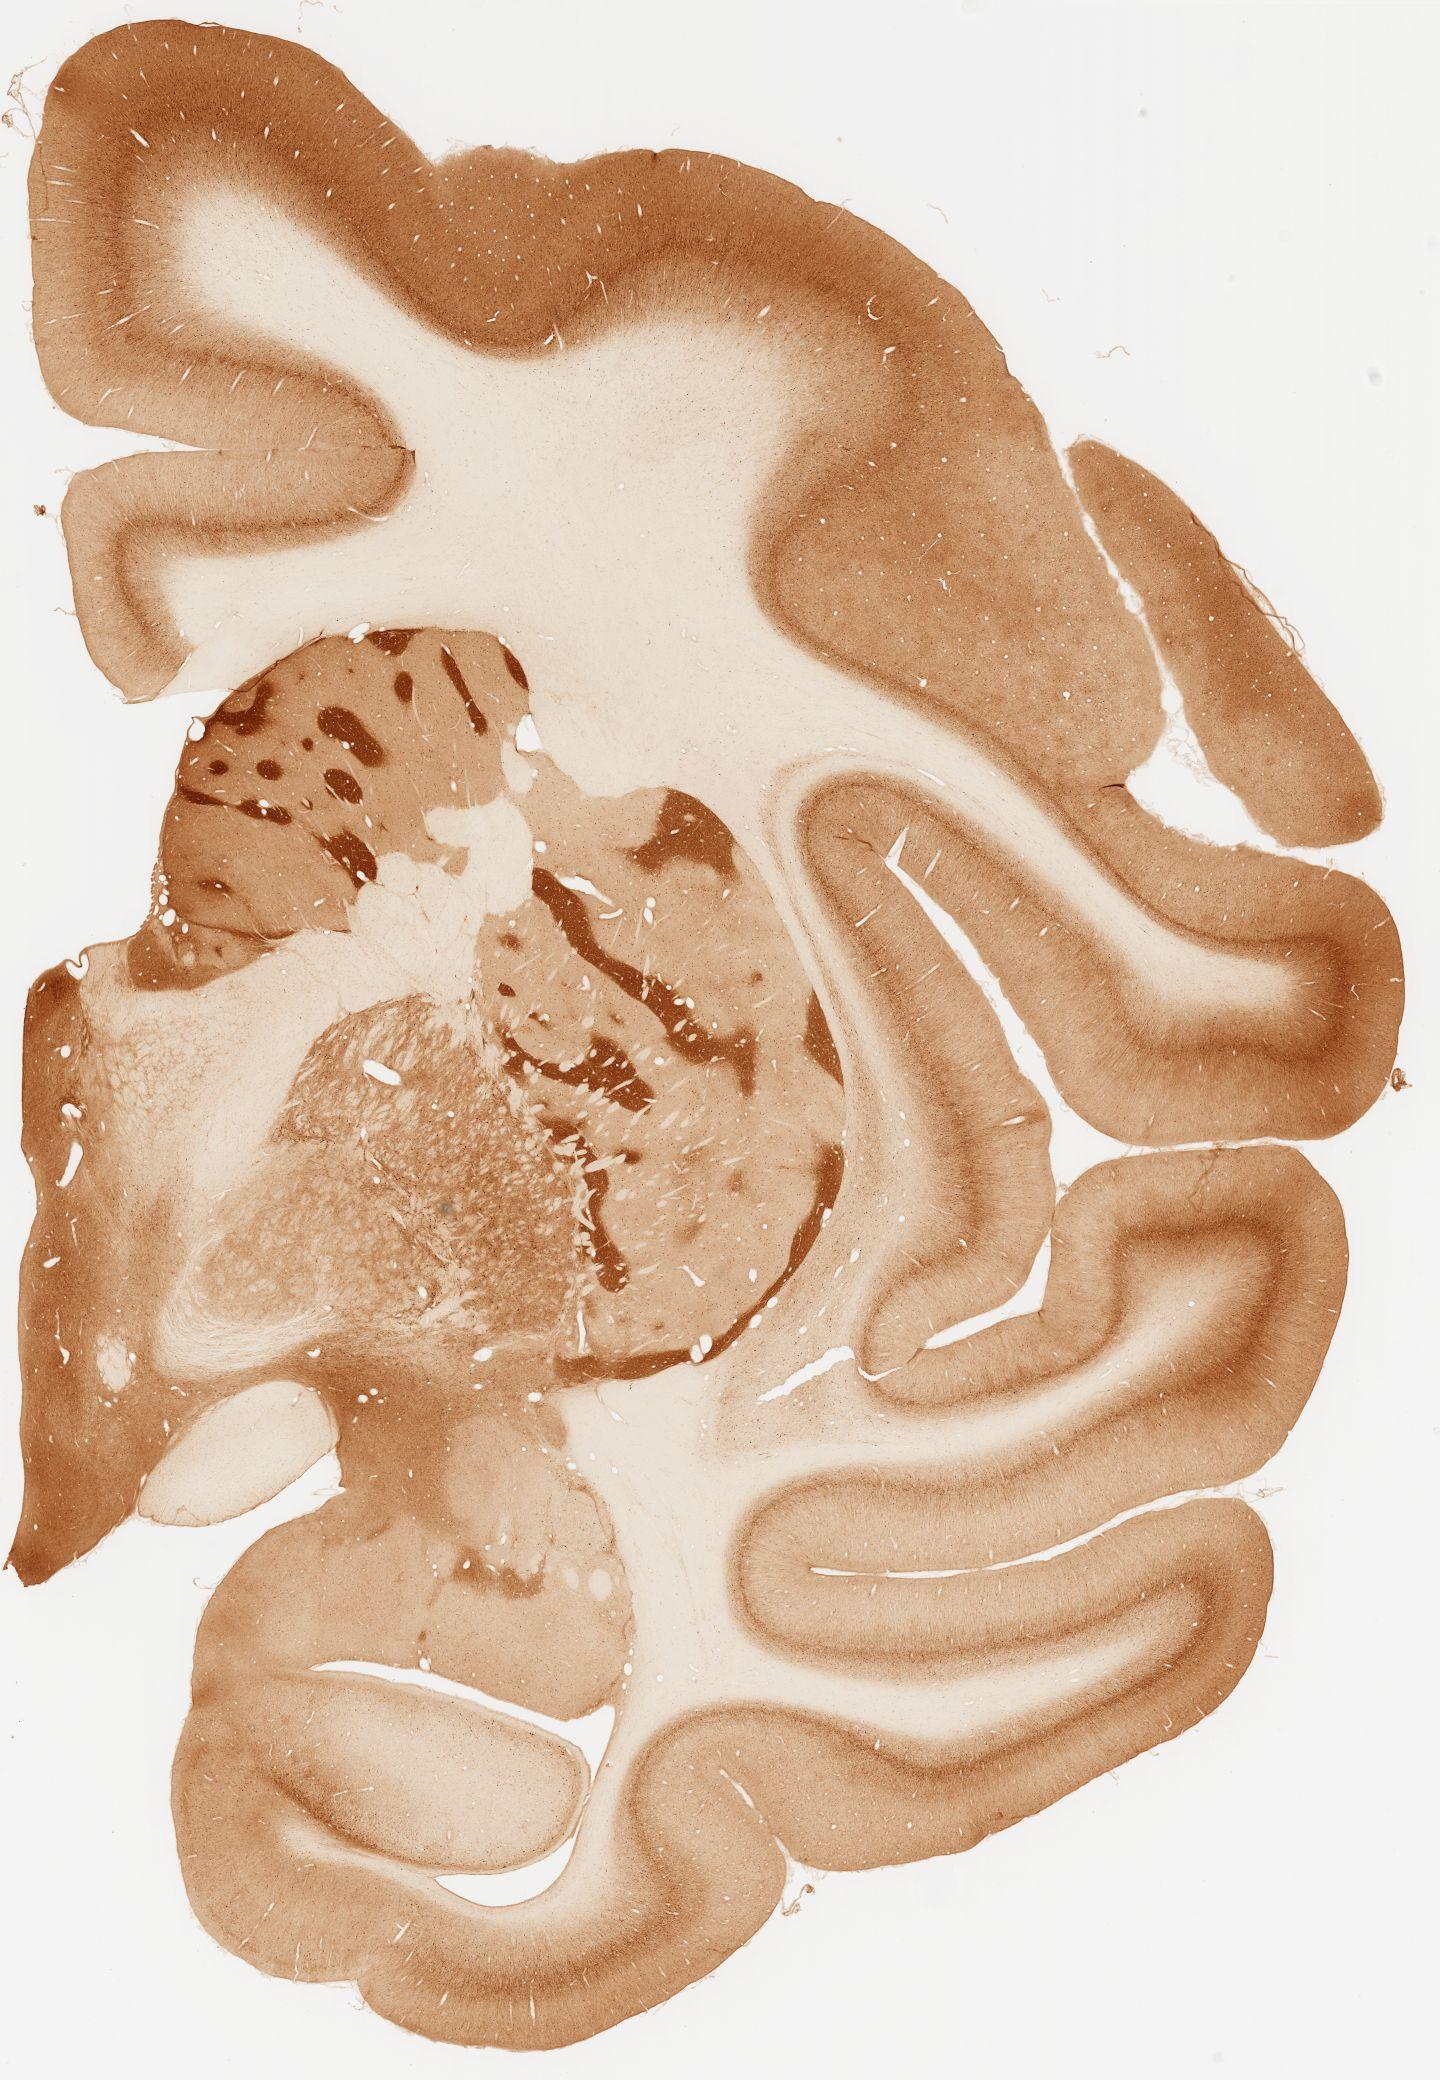

Datasets -> Macaca Fascicularis -> KChIP1, (Potassium Voltage-Gated Channel-Interacting Protein 1), coronal, immuno, Whole-Brain, adult

[ Metadata ]   ·   Source: Edward G. Jones

Displaying Sections 41 thru 80 of 92 Sections for this Dataset